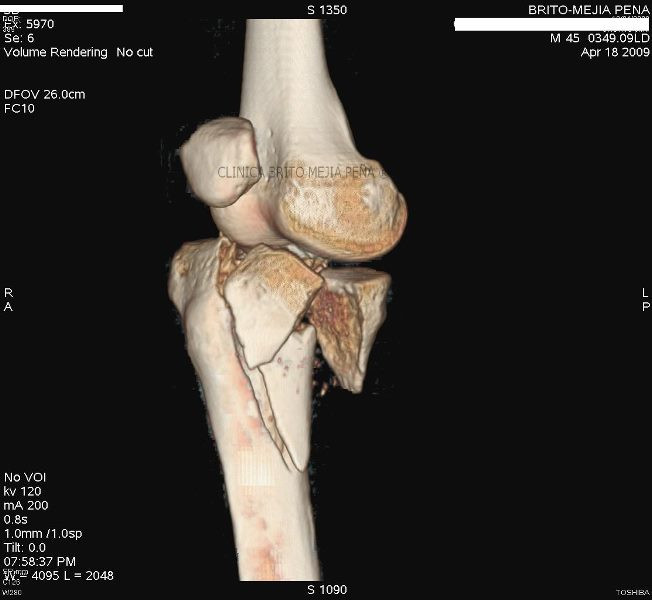

Fractura tibia 3D

Post Image

Fractura tibia MPR